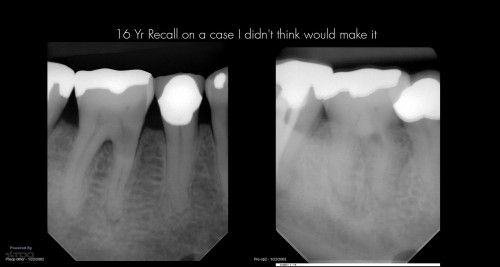

16 yr recall os a fracture

By Gary Carr / July 12, 2018